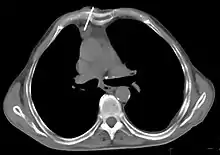

Le scanner thoracique est plus précis que la radiographie thoracique dans le diagnostic des thymomes, en raison d'une plus grande sensibilité envers les masses médiastinales. L'injection de produit de contraste iodé n'est pas forcément nécessaire, mais permet de préciser les rapports du thymome avec les structures vasculaires. Ceci permet à la fois la stadification et de préciser la stratégie chirurgicale lorsqu'elle est envisagée[28].

Les thymomes se présentent comme une masse bien définie du médiastin antérieur, proche du péricarde et dans un plan plus antérieur que les gros vaisseaux intrathoraciques (aorte ascendante et sa crosse, artère pulmonaire, veine cave supérieure). La masse peut être sphérique ou lobulée, mais présente un aspect homogène (plus rarement kystique) qui se réhausse après injection et peut contenir des calcifications[29].

Présentation tomodensitométrique classique d'un thymome à un stade précoce (cercle rouge). À l'arrière, l'aorte, la veine cave supérieure et l'artère pulmonaire sont visibles en coupe.